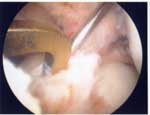

外側円板状半月損傷

外側円板状半月損傷は水平断裂で始まり、強い症状に発展したときは複合断裂になっていることが多くなります。長期経過例では変形性変化を合併することが多くなります(Okazaki 2006)。このタイプの半月板は切れ始めたら正常にできるだけ近い半月板に形成します。手術は関節鏡手術で手術翌日に松葉杖なしで退院出来ます。

完全型円板状半月遊離縁

右:円板状半月